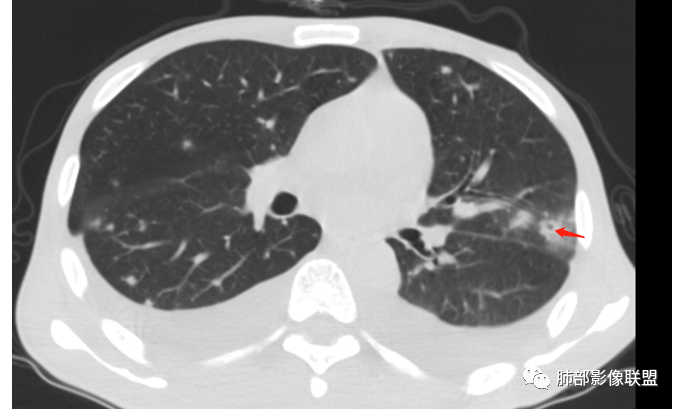

3、左上叶下舌段见沿支气管走形斑片状高密度影,边界模糊

从整体表现,结节的边缘、形态,片状影的改变——支持炎性

2.双肺散在不规则小片状影及结节影,部分可见磨玻璃晕。结节影边界较清楚。左肺片影边界不清,范围较大,支气管相关,支气管壁增厚不明显,病灶内见液化空洞。

1)双肺多发病灶,偶见液化空洞,可能会想到肺炎克雷伯杆菌感染,但病灶边界多较清楚,病灶广泛且患者缺乏呼吸系统临床表现,血压未见明显异常。不大符合肺炎克雷伯杆菌感染等急性感染过程。

3)有恶性肿瘤病史及治疗史,血糖高,属易感人群,两个月内出现片影及肉芽肿样结节影且带磨玻璃晕,出现空洞的,是应当考虑到侵袭性肺真菌病的,如常见的侵袭性肺曲霉病等。注意,这应当是易感人群真菌感染的较为经典的时间段!

念珠菌入侵肺组织后有酵母相转为菌丝相,大量生长繁殖,毒力增强,并夹杂有芽生孢子,引起以多核细胞浸润为主性反应,化脓性改变为主,病灶周围可见菌丝和巨噬细胞浸润,可出现肉芽肿、凝固性坏死、干酪性坏死、空洞、纤维化等。

3.肺炎型肺部影像学表现常为双肺多发片影,肉芽肿样结节影,边界相对清楚,可见磨玻璃晕,部分病灶可显示坏死空洞。部分病例出现胸水。支气管炎型病例可见较广泛支气管壁增厚。